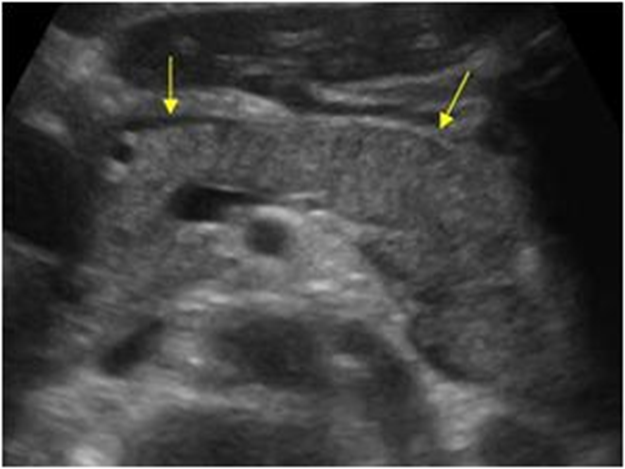

Páncreas hipoecogénico, heterogéneo, de bordes irregulares.

Líquido libre adyacente (Edema)

Hallazgo sugerente: Pancreatitis Aguda

Páncreas heterogéneo con líquido libre peripancreático

Signos de Pancreatitis Aguda.

• Difusa: Aumento de tamaño del Páncreas, disminución de ecogenicidad respecto a parénquima hepático, eco estructura heterogénea. Extra pancreático: Líquido, edema